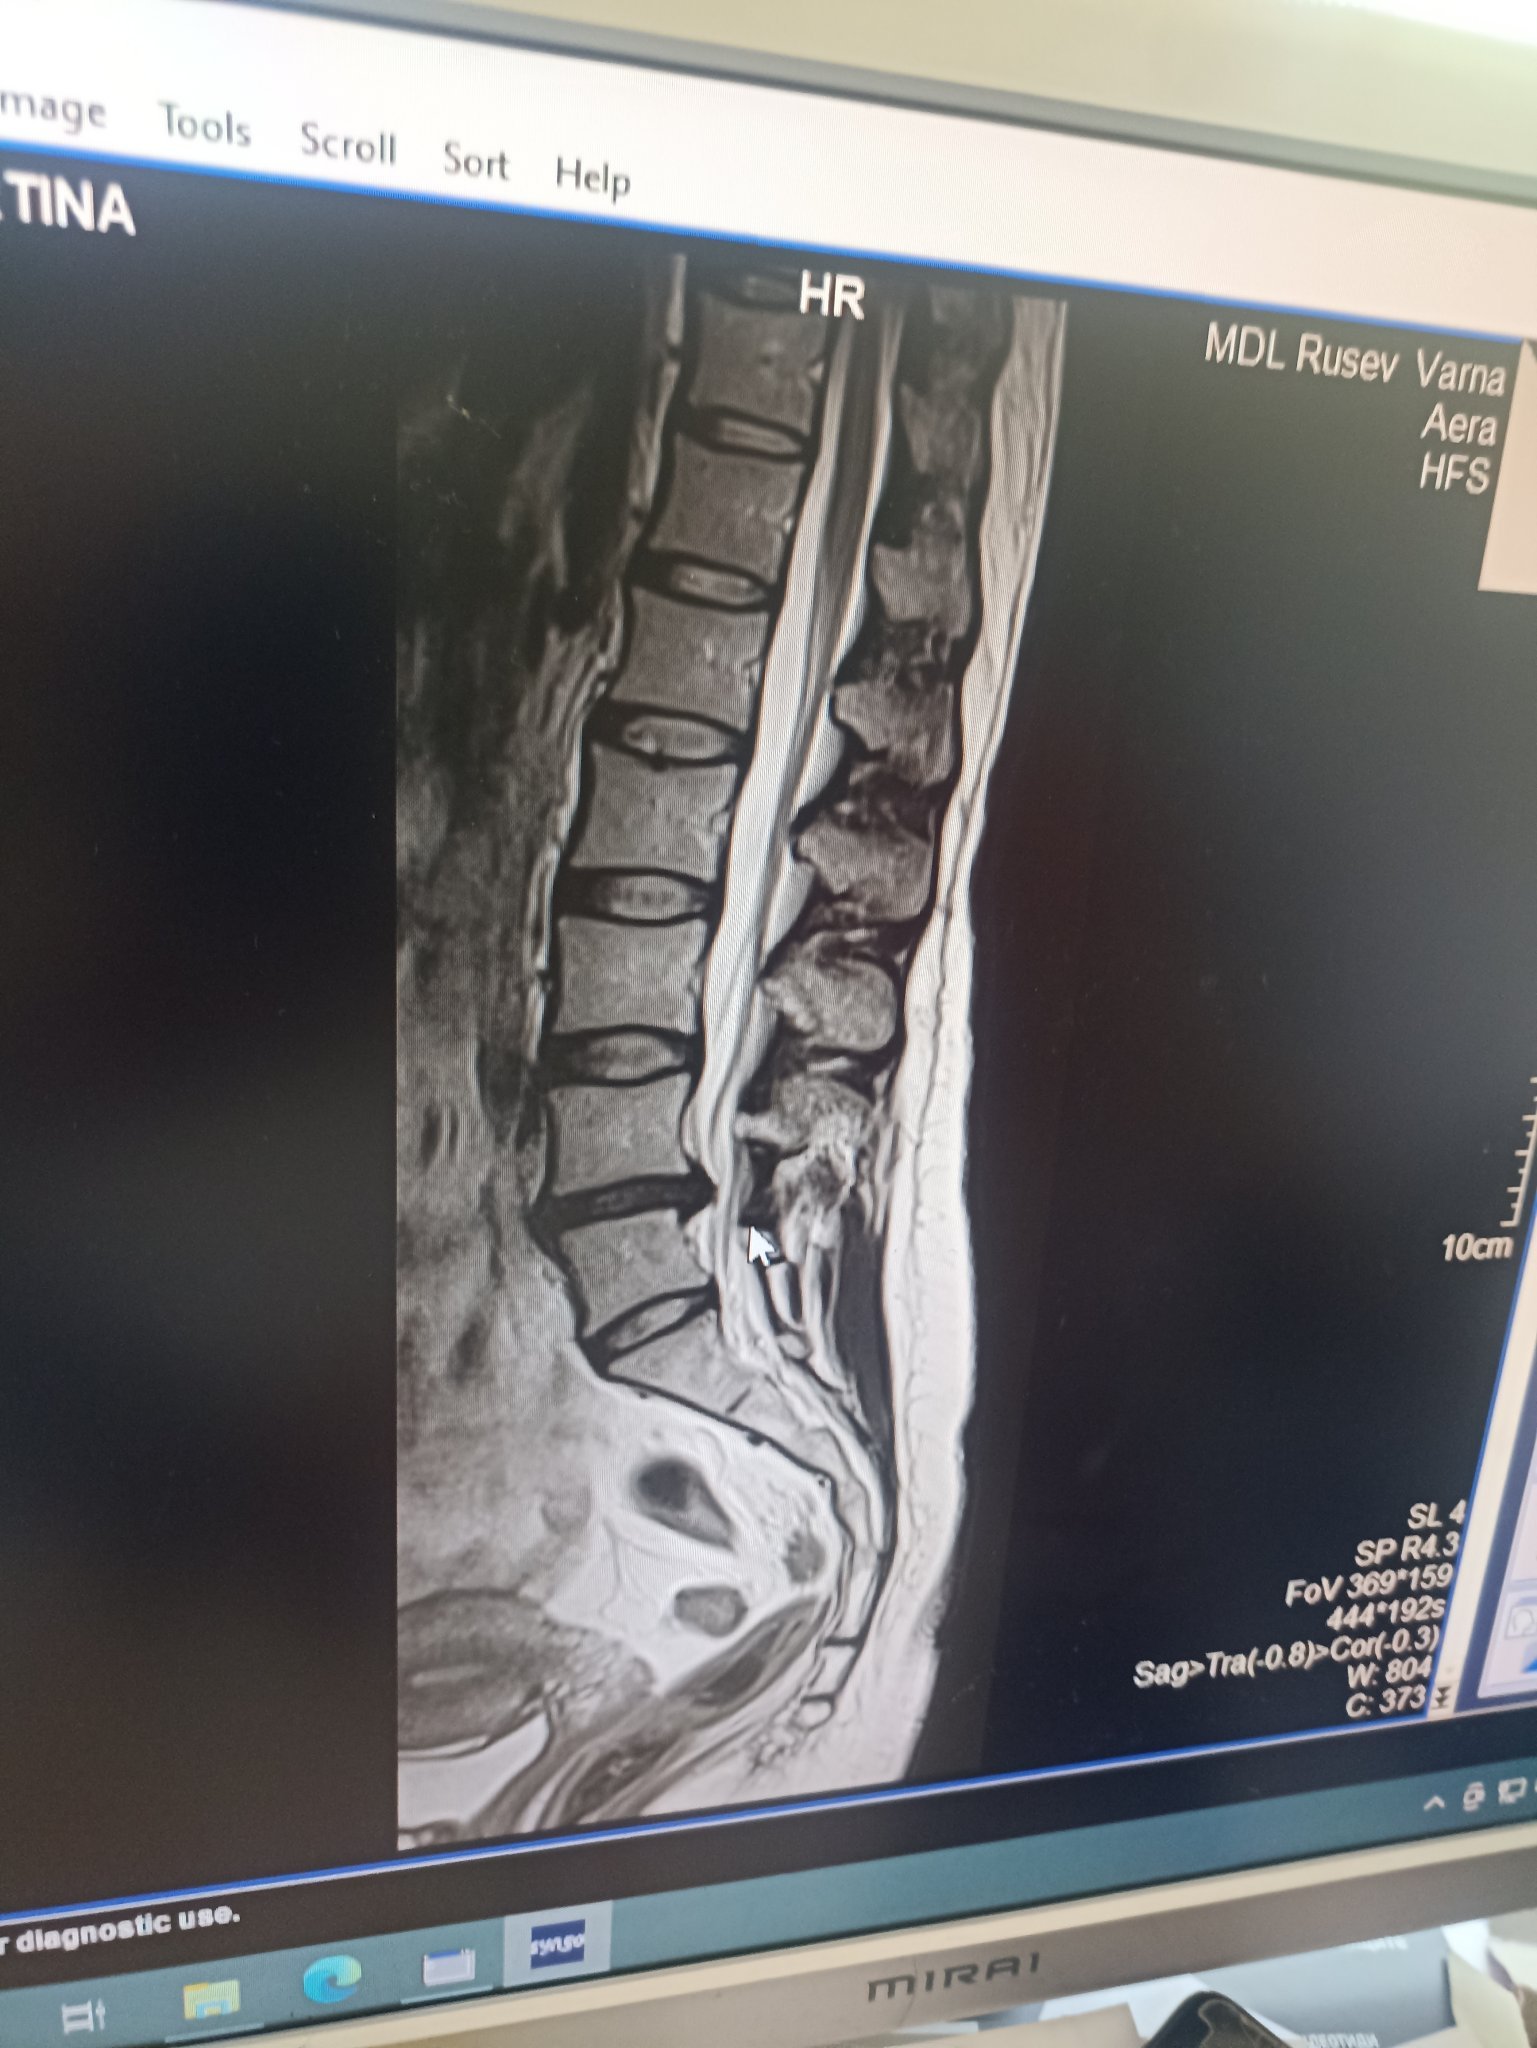

Здравейте. Със силна болка съм от около месец, в началото само в кръста, после премина в десния крак, бедро, задколяно и много силно в прасеца. Подвижна съм, дори когато се движа всъщност по-малко ме боли и се раздвижвам ( куцукайки естествено, бавно и на сравнително къси разстояние) ако направя по-дълга разходка усещам изтръпвания в гръбнака, за крака да не говорим. Много са ми трудни определени движения (лягане, ставане, завъртане в леглото, навеждане, сядане в кола направо невъзможно) да седя седнала абсолютен ужас, дори и след 10 минутно седене после се изправям прегърбена на две и следва 30 минутно разпъване докато успея да се изправя напълно, съпроводено от адски болки по целия крак. За момента съм посетила ортопед, невролог, физиотерапевт, множество кинезитерапевти. Последните са на мнение, че за момента са безсилни и че трябва първо горните специалисти да се погрижат за възпалението и спад на отока, та чак тогава да се намесят кинезитерапевтите. Бях на няколко вида НСПВ и две инжекции флостерон - абсолютно никакъв резултат. сега пия НСПВ, гастропротектор, тиогама и мидокалм. Болката не се променя, но се надявам все нещо да се случва с възпалителния процес бавно, но славно. Прилагам резултат от ЯМР - в понеделник съм на невролог за преглед на снимката. Според физиотерапевта, първо започвам с лазер и магнитно поле след това физио. Какво бихте споделили за тези лазер процедури, притеснявам се да не влоши някак възпалението. Казаха ми, че най-лошият сценарии е просто да няма ефект. Физиотерапевтката не мисли /говори/ очаква да се стига до операция.

Fearful аз си мислех, че моята е средна към голяма (7 мм) и се мъча с нея вече втора година, но тази твоята ми изглежда наистина голяма (гледайки сагиталния разрез), пристискаща канала. Понеже си с изгладена лордоза (сакрумът ти е извит почти в хоризонтално положение) нормално е да те боли седнала (целия товар го поема гръбнака до извивката на S1), дискът направо е поддал и се е сплескал като кюфте. Седнала ли си работила до сега? Би трябвало в легнало по гръб положение със свити крака или с вдигнати на стол или възглавница на 90 градуса свити крака да ти се успокоява болката малко. С въздушни екстензии също можеш да пробваш да декомпресираш. Колкото повече се натиска вертикално кюфтето, толкова повече стеснява пространството отзад и пристиска нервите.

Според мен това не са 4.3 мм. Но по-добре неврохирург да види снимките ти (сагитално и аксиално). Вижда се голямо издуване, но хернията фораминално трябва да се види на аксиален разрез.